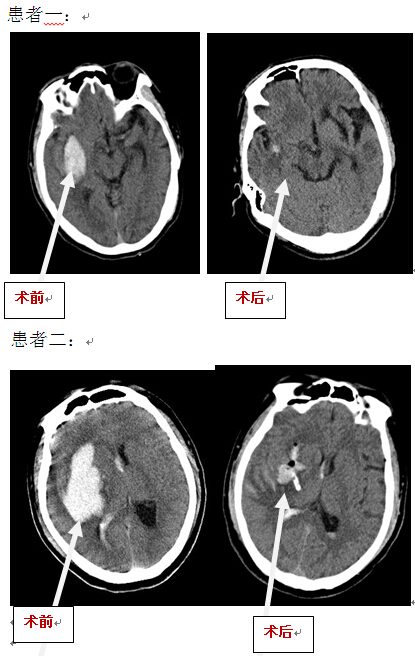

2014-11-05高血壓性腦出血最新療法

高血壓性腦出血(HICH)多發(fā)生于有高血壓病史的中老年人,是神經(jīng)外科最常見(jiàn)的急重癥之一,其致死率和致殘率很高。雖然近百年來(lái)人們從未間斷地對(duì)該病進(jìn)行研究探索并積累了豐富的經(jīng)驗(yàn),但其死亡...閱讀全文